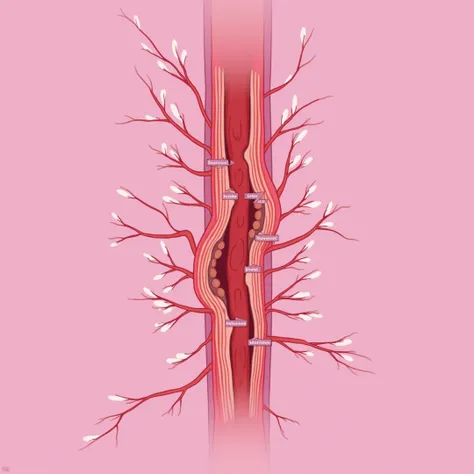

A diagram of the anatomy of the human body